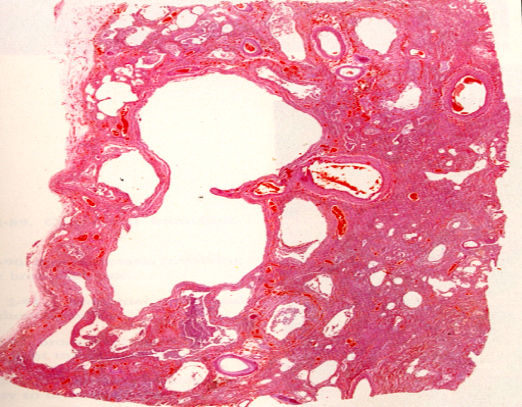

3. 病理变化

病变的支气管可呈囊状或筒状扩张(图3-2),病变可局限于一个肺段或肺叶,也可累及双肺,以左肺下叶最多见。扩张的支气管、细支气管可呈节段性扩张,也可连续延伸至胸膜下,扩张的支气管数目多少不等,多者肺切面可呈蜂窝状(图3-3)。扩张的支气管腔内可见粘液脓性渗出物或血性渗出物,若继发腐败菌感染可带恶臭,支气管粘膜可因萎缩而变平滑,或因增生肥厚而呈颗粒状。

图3-2

图3-3

支气管壁呈慢性炎症改变伴不同程度组织破坏。粘膜上皮可萎缩、脱落或增生、鳞状上皮化生,亦可有糜烂或溃疡形成,支气管壁平滑肌、弹力纤维及软骨萎缩变性,甚至完全消失,管壁被炎性肉芽组织所取代,并可见淋巴细胞、浆细胞、嗜中性粒细胞浸润。扩张支气管周围纤维组织增生,逐渐发生纤维化(图3-4)。